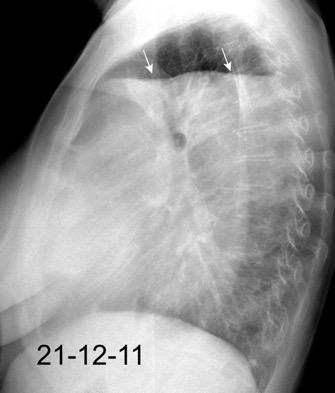

Marzo 2014: Perforación longitudinal distal secundaria a episodio de vómito (síndrome de Boerhaave). Derrame pleural izdo. que evoluciona a empiema.

Wang C-T et al. Tension hydropneumothorax in a Boerhaave syndrome patient: A case report . World J Emerg Med, 2021. Katabathina V et al. Nonvascular, nontraumatic mediastinal emergencies in adults:a comprehensive review of imaging findings. Radiographics. 2011.